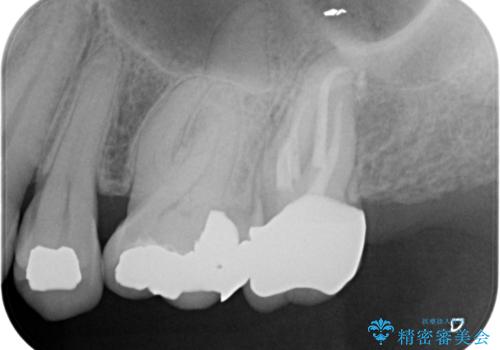

痛みはないとの事でしたがレントゲンを撮影したところ根の先に病巣がある事がわかりました。

被せ物、古い材料を徹底的に除去し、ラバーダム防湿にて無菌的処置を行い、セラミックの被せ物で治療を行いました。

治療が終了してからも定期的にレントゲンをとり経過観察を行いました。

病巣は現在縮小しておりまた白い被せ物が入り患者様に満足してもらえました。